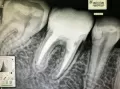

Доброго времени суток. Скажите пожалуйста: если болели зубы при накусывании в течение 2-х дней, болели не сильно, а потом прошли, то что это может быть? Спасибо.

Добрый день. В этом случае возможно на верхушках имеется воспаление. И оно, как правило, проявляется при снижении иммунитета. Я вам рекомендую обратится на очный прием к стоматологу-терапевту для составления плана лечения оперяясь на рентген снимки и на состояние зубов в полости рта. Запишитесь к нам на прием и мы обязательно вам поможем.